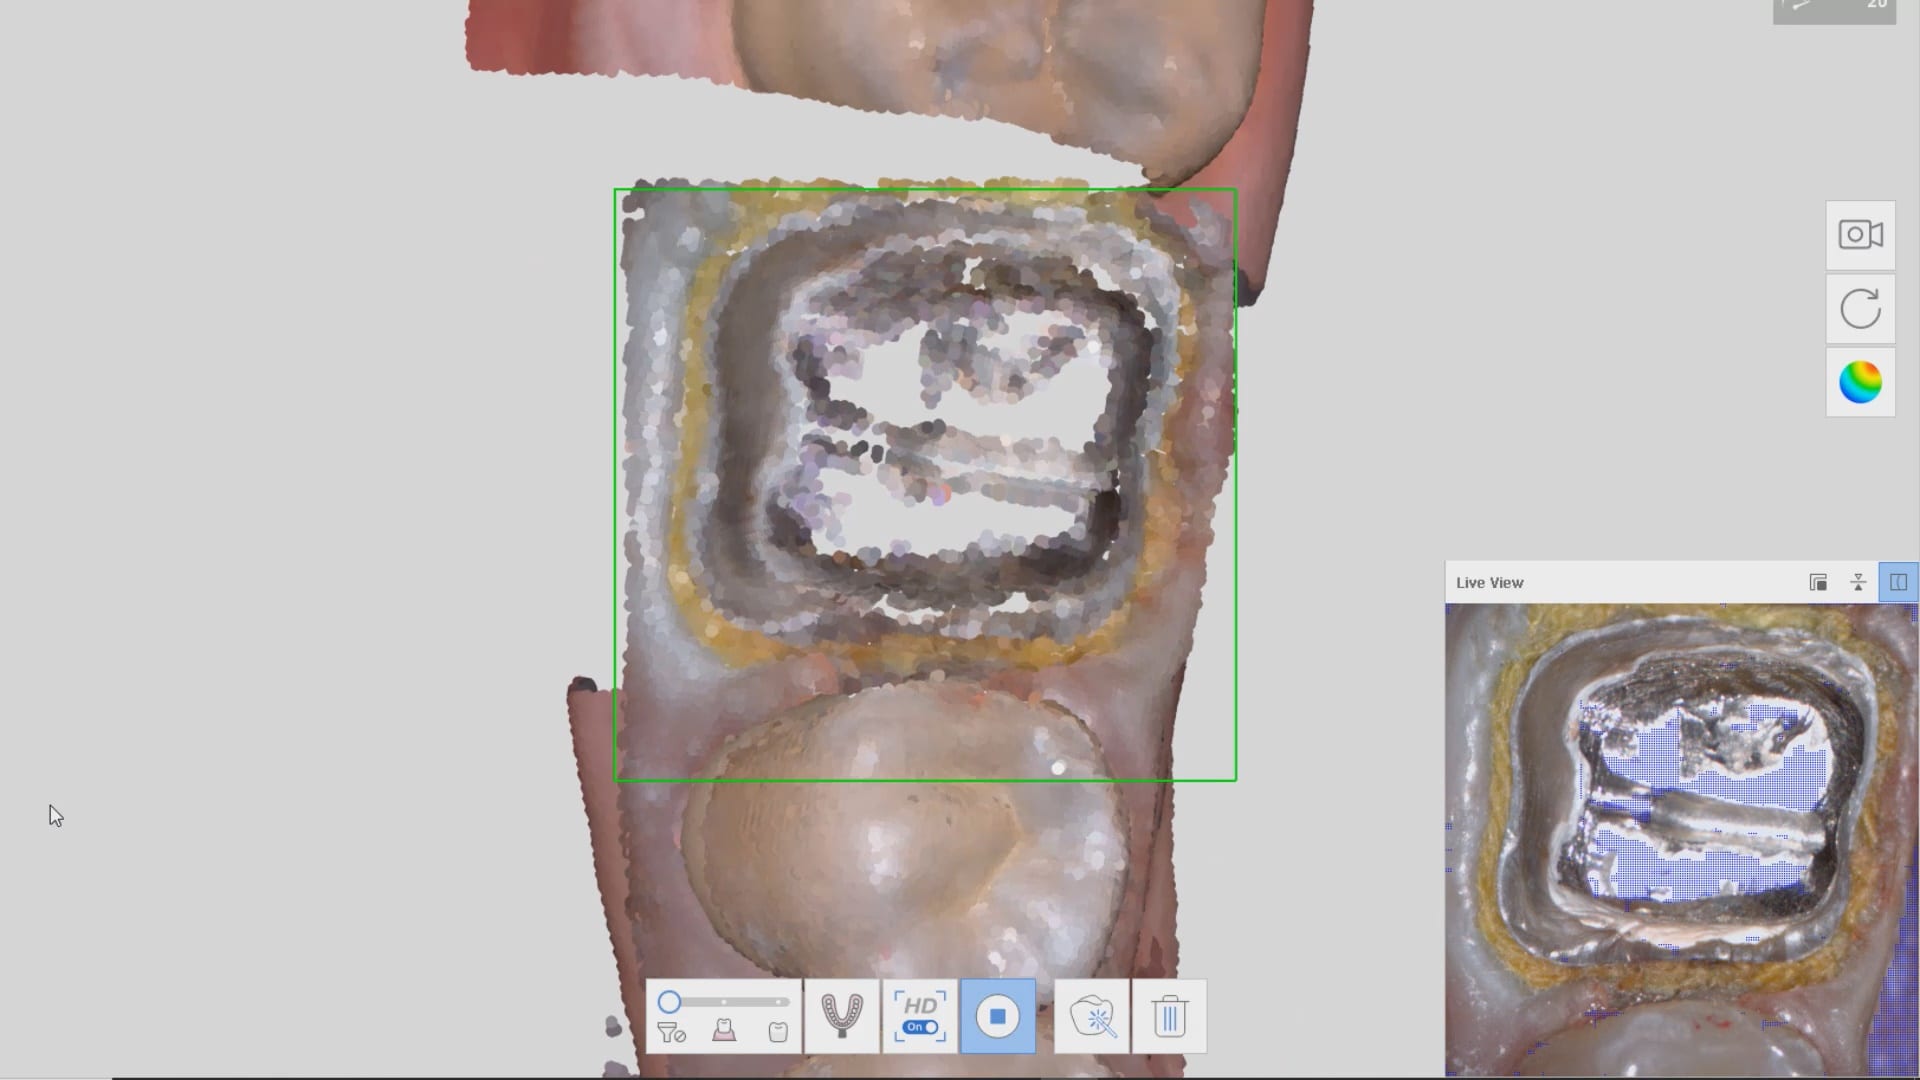

In this clinical video we demonstrate how to scan a molar preparation for the replacement of a crown with recurrent decay and open margins. The molar was root canal treated and the tissue was inflamed. the preparation was imaged and a temporary was fabricated to allow the tissue to heal properly.

The main point of this video is to show how to capture the contacts of the adjacent teeth and the deep marings